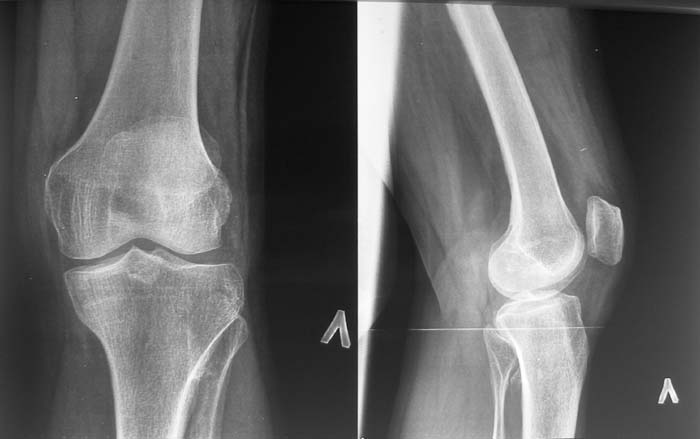

Женщина, 55 лет. С 2002 года - гонартроз. В настоящее время - боли в коленном суставе, стартовые боли, иногда в ночное время (проходит <от перемены положения ноги>).

Принимает НПВС, артрон-комплекс, внутрисуставно гиалган. Ревмопробы отрицательные. На рентгенограмме отметили сужение шейки малоберцовой кости, на спиральной КТ - экзостоз? Ваше мнение о целесообразности операции (велика вероятность повреждения нервов), предварительной биопсии?Спасибо! С уважением, А.В.Владзимирский Донецкий НИИ травматологии и ортопедии Донецк, Украина

Если боли связаны с гонартрозом, то показано тотальное эндопротезирование коленного сустава. Тип эндопротеза - мыщелковый, с сохранением задней крестовидной связки, сейчас таких моделей много (LCS, Balansis, Genesis, Scorpio, КЭКС-01 и другие, всё зависит с какими фирмами Вы работаете). Вопрос об удалении остеохондромы спорный, с одной стороны маловероятно ожидать у женщины 55 лет быстрого перерождения во вторичную хондросаркому при такой рентгенологической картине. Можно спротезировать коленный сустав и проводить рентгенконтроль каждые 6-12 мес. С другой стороны, если спротезировать и оставить остеохондрому, а она начнёт интенсивно рости, то её последующее радикальное удаление может ослабить тибиальный компонент эндопротеза. Проявляя онкологическую настороженность, остеохондрому лучше удалить первым этапом, до эндопротезирования с интервалом между операциями 6 мес. Производить биопсию в данном случае однозначно не целесообразно, так как при перерождении остеохондромы во вторичную хондросаркому на начальных стадиях малигнизации трудно гистологически отличить "добро" от "зла", и в этих ситуациях приоритет отдаётся рентгенологическим признакам. Техника операций при подобной остеохондроме стандартная - краевая резекция. Опасность повреждения малоберцового нерва существует всегда, но она зависит от мастерства хирурга и наличия микрохирургической техники (микроскоп не обязателен :)).

Насчет протезирования коленного сустава - при таком сохранном суставе навряд ли можно согласиться и совершенно согласен с Яковом, что надо искать источника боли сканированием или магнеторезонансными исследованиями.

Действительно, надо бы определиться в причине болевого синдрома. Подобные остеомы, как правило, немые. Болевой синдром может быть связан с околосуставнойт патолоией (например, поражение "гусиной лапки") или внутрисуставной. По R - граммам сустав очень даже сохранный (протезировать его явно нет необходимости), а отвергнуть внутрисуставную патологию или сразу ее максимально устранить поможет артроскопическое вмешательство. Повреждения менисков частенько симулируют остеоартроз.

Суставная щель на вид очень даже приличная. Мне кажется у больной есть варусная деформация колена, и возмможно с этим связано дегенаративное поражение медиального мениска и вся клиническая картина. Если это так, то эндопртезирование это слишком! Может что полегче: артроскопия и медиальная плюс-остеотомия.

Экзостоз скорее всего случайная находка, но динамического наблюдения безусловно требует.